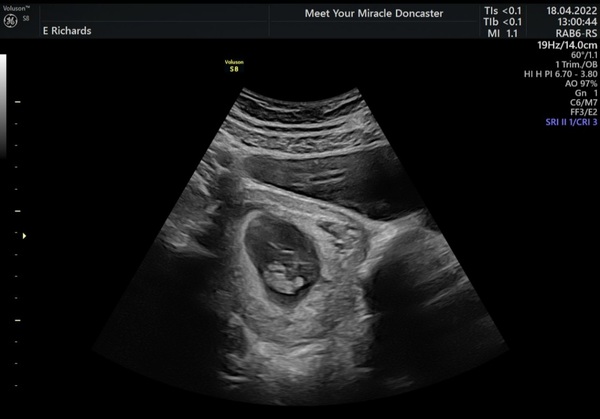

@rsmamaa here's the photo ❤

Will catch up on all the messages but just thought I'd say everything was okay! Measuring 7+1 which is exactly where I thought anyway and saw a very fast little heartbeat ❤️🥰. No idea what caused the spotting/ brown discharge but baby is fine. I'll still go for the NHS one as it would probably be good to have things on record but so pleased we did this one for reassurance!